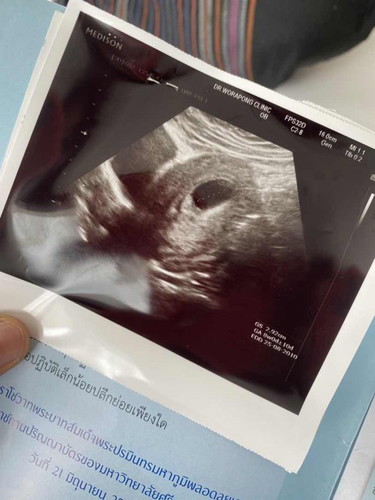

10 สัปดาห์.

สอบถามหน่อยคะ. ตอนนี้ 10 สัปดาห์แล้วแต่ยังไม่พบตัวอ่อนเป็นอะไรมั้ยคะ. หมอบอกรอดูเดือนหน้า

มีโอกาสเจอน้องถึง 12 วีคค่ะ ถ้าเกินนี่ท้องลม